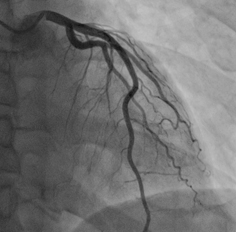

心臓カテーテル検査の冠動脈造影等の血管撮影のシネフィルムを電子化しデジタル動画として活用可能となります。電子データはDICOMフォーマット/MP4/AVI形式に変換いたします。患者ID/患者名/検査日等情報も管理属性として付与いたします。

動画の再生環境に応じてDICOM/MP4/AVI形式に変換いたします。患者ID/患者名/検査日等の管理属性を付与いたします。